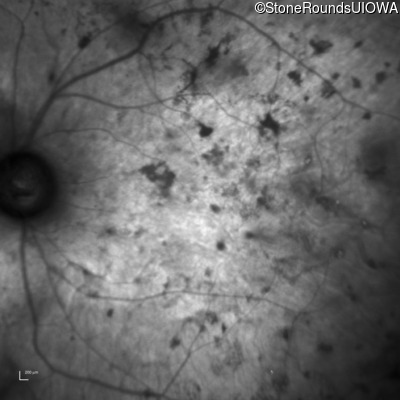

Visit at age: 51 years

Fundus Photography - Right - Light Perception

Exemplar

Fundus Photography - Left - Light Perception